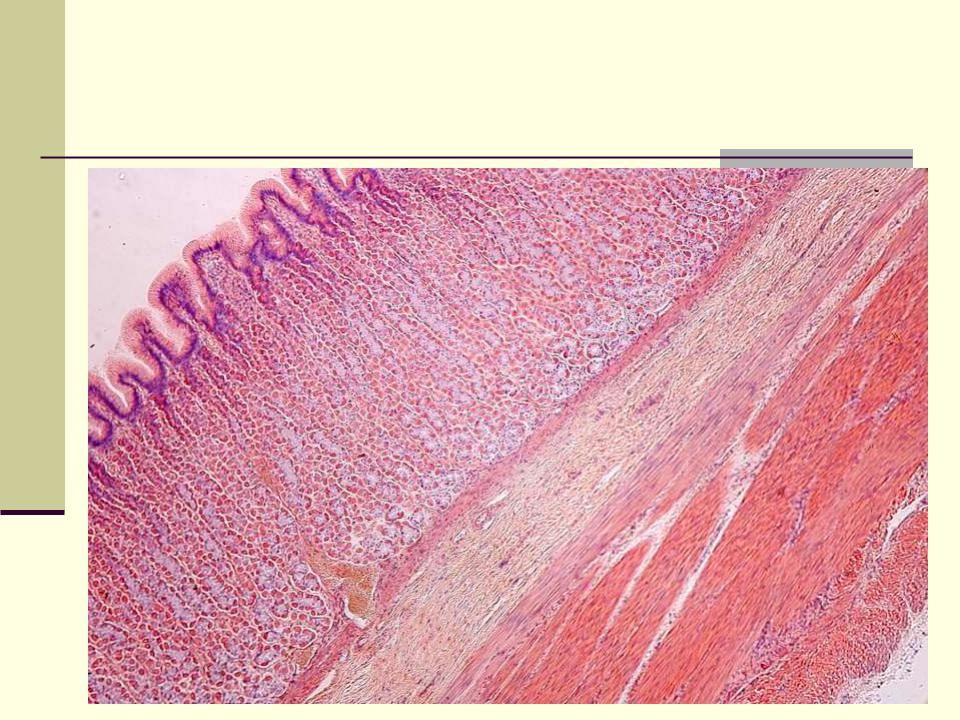

Желудок (малое увеличение)

ТОНКАЯ КИШКА

Слизистая

оболочка

Подслизистая

основа

Мышечная

Серозная